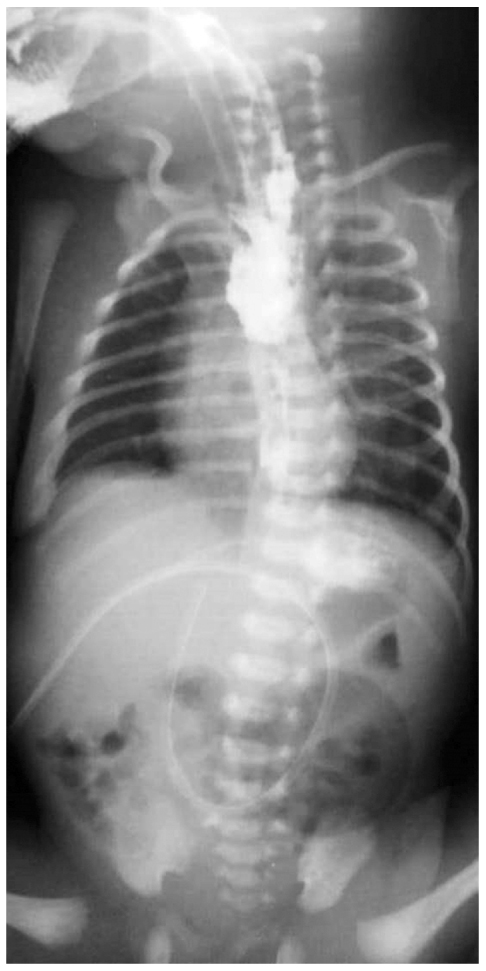

Описание исследования

У 7 детей (78%) сразу после рождения возникли сложности с интубацией трахеи, у 4 пациентов (44%) отмечены трудности в постановке желудочного зонда. Диагноз перфорации пищевода был установлен в 1–5-е сут жизни. В клинической картине преобладали явления нарастающего респираторного дистресса, а также слюнотечение и кровянистое отделяемое из ротоглотки (n=6). В наиболее тяжёлых случаях (n=2) дыхательная недостаточность прогрессировала из-за нарастающего гидроторакса, у 1 ребёнка появились признаки перитонита и отёка тканей забрюшинного пространства. Миграция желудочного зонда в брюшную полость в последнем случае была заподозрена не сразу, и ребёнка начали кормить. К запоздалой диагностике осложнения привело отсутствие «привычки» отслеживать правильность стояния желудочного зонда, как мы поступаем по отношению к внутривенным, перидуральным катетерам, интубационным трубкам. Именно поэтому необходимо знать и помнить о возможности перфорации пищевода у недоношенного ребёнка и при малейшем подозрении незамедлительно проводить диагностический поиск. Он складывается не только из оценки появившихся симптомов (саливация, дисфагия и пр.), но и обязательного ультразвукового и рентгенологического обследования ребёнка для определения положения желудочного зонда в грудной клетке и брюшной полости, а также выполнения рентгеноконтрастных исследований. В ряде случаев только внимательная оценка рентгенограммы, иногда уже ретроспективно, позволяет поставить правильный диагноз (рис. 1).

Рис. 1. Обзорная рентгенография органов грудной и брюшной полости: конец желудочного зонда располагается под диафрагмой справа от входа в желудок (случайная находка, снимок назначен на фоне ухудшения состояния ребёнка)

Fig. 1. Plain thoracic and abdominal radiography: the distal tip of nasogastric tube is located beneath the diaphragm, to the right from the gastric cardia. This was an ‘occasional finding’, that X-ray being administered because of deterioration of general condition of baby

Рентгенологическая картина миграции желудочного зонда из просвета пищевода в окружающее пространство может быть различной и мало зависеть от локализации самой перфорации (рис. 2–4). Затёк контрастного вещества в плевральную или брюшную полость, средостение или забрюшинное пространство мы встречали при перфорации грушевидного синуса, глоточно-пищеводного перехода и нижней трети пищевода.

Рис. 4. Обзорная рентгенография органов грудной и брюшной полости: желудочный зонд расположен под диафрагмой вне желудка

Fig. 4. Plain thoracic and abdominal radiography: nasogastric tube tip is located beneath the diaphragm, without the stomach